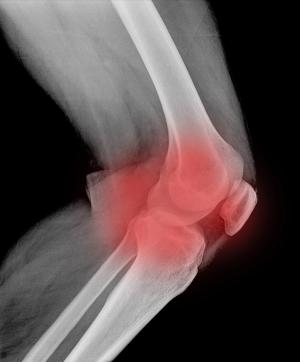

A new study found no major structural effect on the knee joint after 2 years of intra-articular steroid injections.